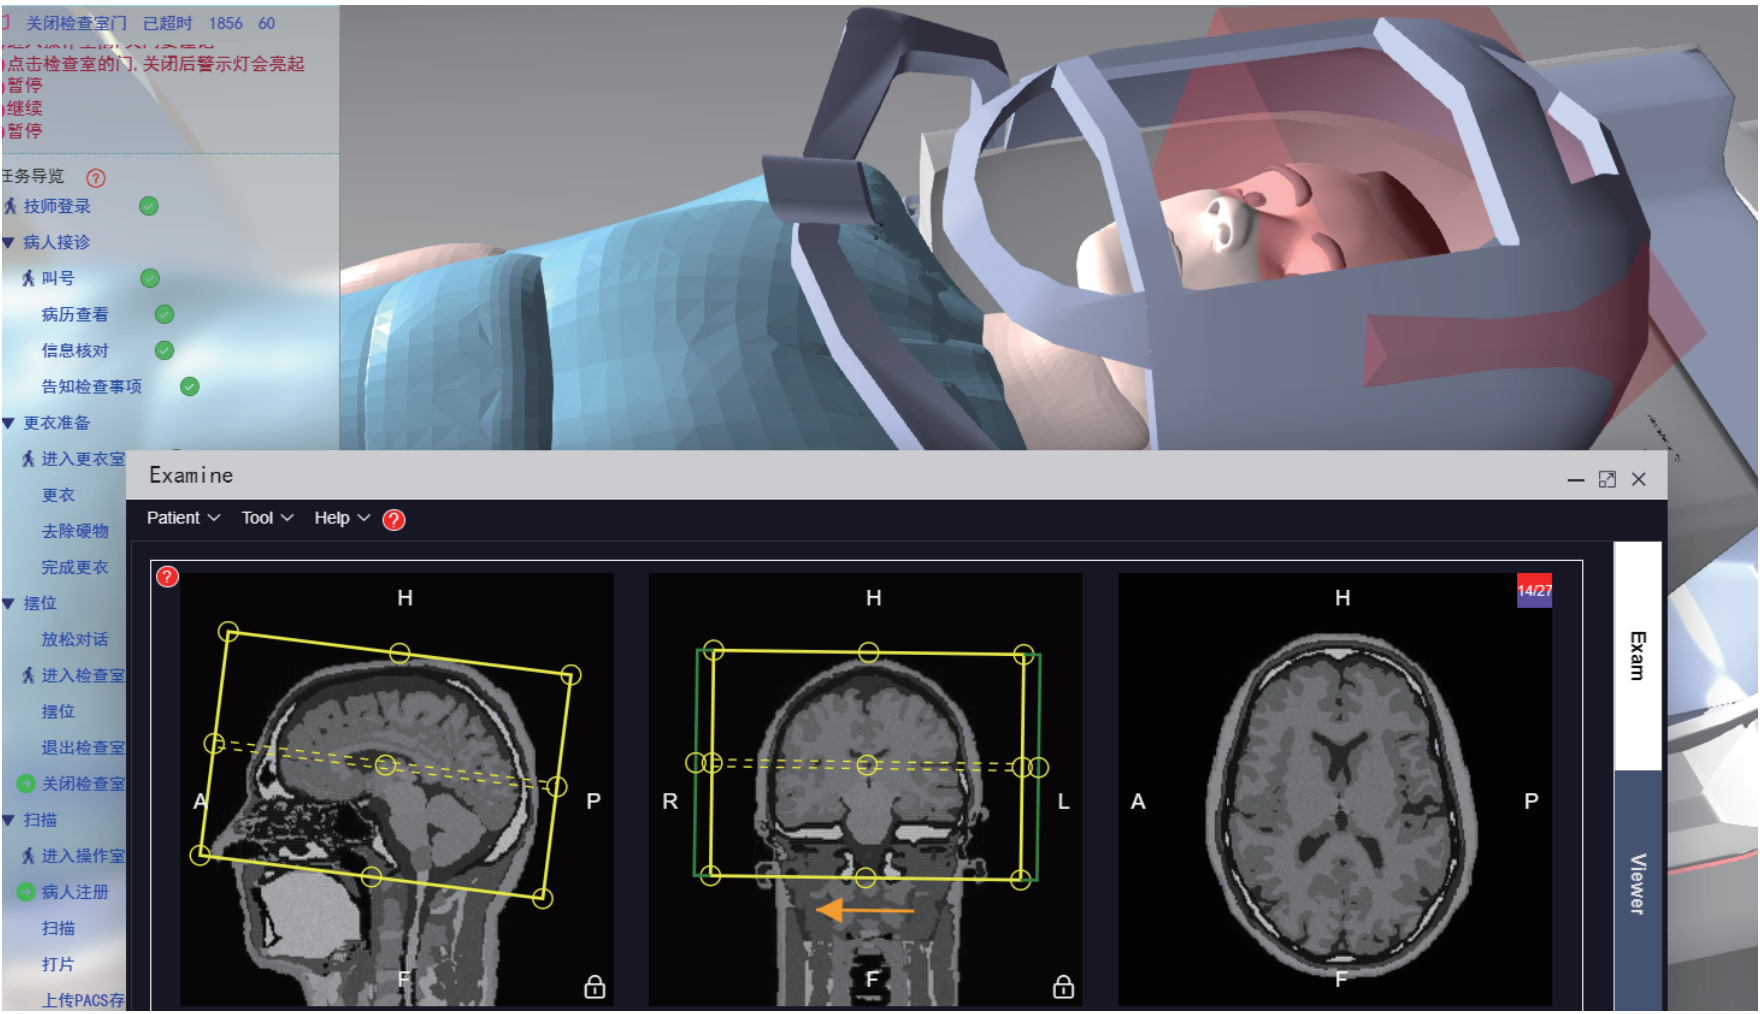

基于数字孪生技术,研发了MRI成像数字孪生系统,模拟常见影像设备,设备操作与真实设备相同,达到使用者如同使用真实设备的效果。本场景基于真实的核磁检查流程所设计,扫描过程根据物理数字人实时计算MRI图像,包含参数可调、伪影模拟、故障诊断等各种强大功能。

基于数字孪生技术构建的 MRI 检查技术模拟系统,实现了机理与场景的深度融合,操作逻辑与真实设备完全一致,打造高度逼真的虚拟检查环境。虚拟场景完整复现 MRI 检查全流程,从技师登录、叫号、查验检查单、引导患者更衣等事项,到线圈选择、摆位、序列与参数设置等环节均细致还原。

系统内置基于人体摆位和参数的标准数据库(数据源自临床规范与专家共识),可对操作全过程进行精准量化评分,确保实训考核的标准化。此外,系统支持模拟灯芯绒伪影、化学位移伪影、运动伪影等十余种常见伪影,并可针对不同伪影设置考核场景,要求操作者制定并执行相应处理方案,强化对影像质量控制能力的培养,助力医学影像技术专业学生提升临床实操与问题解决能力。

操作场景与成像深度融合